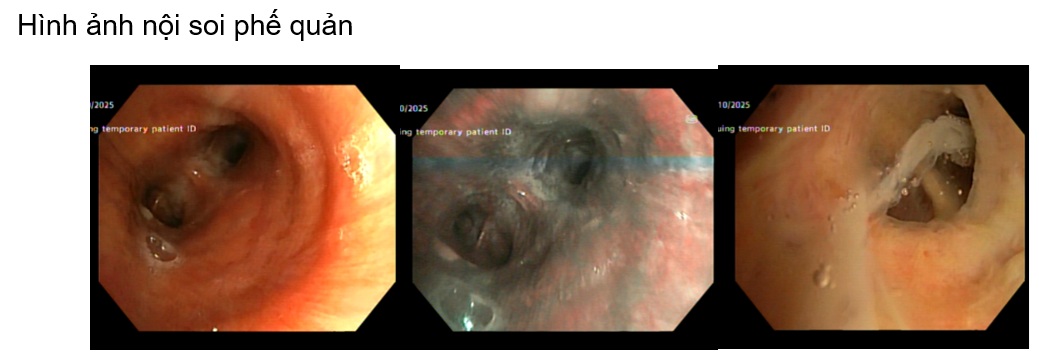

Một trường hợp lâm sàng tại khoa Nội tổng hợp, bệnh nhân nam L.V.R 80 tuổi, vào viện vì sốt, tiêu lỏng kèm khó thở, nặng ngực. Tiền sử tăng huyết áp, chưa ghi nhân bệnh lý hô hấp, bệnh mạn tính khác trước đó. Bệnh nhân nhập viện với tình trạng nhiễm trùng nhiễm độc, tổn thương thận cấp. Trong quá trình nằm viện bệnh nhân khó thở tăng dần suy hô hấp, sốt cao dao động 39 – 400C, đáp ứng kém với phác đồ kháng sinh ban đầu (piperacillin/tazobactam + levofloxacin). Bệnh nhân được nội soi phế quản, sau 5 ngày nhập viện kết quả cấy dịch rửa phế quản Candida albican, bệnh nhân được chỉ định phối hợp sử dụng kháng nấm anidulafungin. Sau 4 ngày sử dụng kháng nấm, lâm sàng bệnh nhân cải thiện hết sốt, ngưng được oxy, thở đều êm, chức năng thận hồi phục.

Bệnh nhân được tiếp tục duy trì phác đồ kháng nấm anidulafugin và fluconazole (hạ bậc kháng nấm), trong quá trình điều trị bệnh nhân được khám chuyên khoa mắt, theo dõi men gan, chức năng thận, bilan nhiễm trùng cũng như hình ảnh học (CTscan ngực, xquang ngực thẳng). Dưới đây một vài hình ảnh học trong quá trình điều trị nội, ngoại trú.